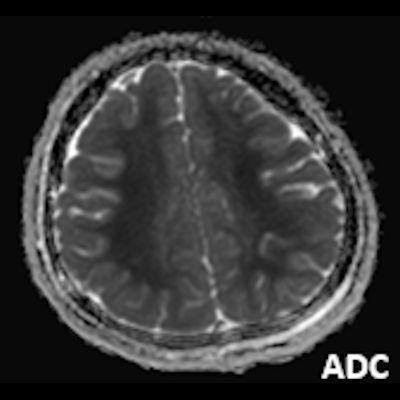

- A) Bilateral serebral kortekste (oklar) ve bazal ganglionlarda (oklar) yaygın DAG hiperintens, ADC hipointens difüzyon kısıtlamaları görülüyor.

- B) 9 gün sonraki difüzyon MR incelemede kortikal ve bazal ganglionlardaki difüzyon kısıtlamalarının gerilediği, bilateral serebral beyaz cevherde (oklar) ve internal kapsül arka bacağı- kortikospinal trakt boyunca (oklar) yaygın DAG hiperintens, ADC hipointens difüzyon kısıtlamalarının geliştiği izleniyor.